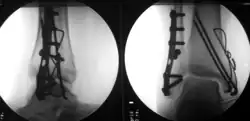

Aufgrund der Biegsamkeit der Drähte und der nicht formschlüssigen Verankerung der Drähte im Knochen ist das Operationsergebnis in der Regel nicht bewegungsstabil, sodass weitere Ruhigstellungsverfahren, z. B. Gipsverband oder auch der hier illustrierte Fixateur externe zur Anwendung kommen müssen.

Bei der hier dargestellten Handgelenkfraktur war eine bewegungsstabile Versorgung z. B. mittels winkelstabiler Platte (s. u.) aufgrund der hochgradigen Osteoporose und der erheblichen Weichteilschädigung nicht sinnvoll, daher erfolgte die geschlossene Reposition mit Kirschnerdraht-Fixierung und zusätzliche Ruhigstellung mit Fixateur externe. Eine Gipsruhigstellung wäre hier ebenfalls aufgrund der schlechten Weichteilverhältnisse nicht möglich gewesen.

Vorteil der Kirschnerdraht-Fixierung ist der geringe Verfahrensaufwand und die geringe Invasivität. Die Entfernung der Drähte erfolgt in der Regel unmittelbar nach Abschluss der Frakturheilung (also nach ca. 4 bis 6 Wochen).

Nachteil der Kirschnerdraht-Fixierung ist die Kombination der Risiken eines invasiven Eingriffes (Infektion, Narkoserisiko) mit den Nachteilen einer längeren Ruhigstellung (Muskelatrophie, Einsteifung des Gelenkes, keine frühfunktionelle Behandlung möglich).

Spezifische Komplikationen und Risiken sind „Wandern“ der Drähte, Drahtbruch und Korrekturverlust.

Fixateur externe

Ein wichtiges Instrument zur Fixierung einer Fraktur ohne Manipulation an der Fraktur selbst ist der Fixateur externe („äußerer Spanner“). Grundprinzip seiner Anwendung ist das frakturferne perkutane Einbringen mehrerer kräftiger Schrauben (Schanz’sche Schrauben oder auch die nach Fritz Steinmann benannten Steinmann-Nägel), die mittels Stangen und justierbarer Montageelemente miteinander verbunden werden.

Der Fixateur externe kommt alleine oder in Kombination mit anderen Verfahren wie oben dargestellt in vielfältigen Situationen zur Anwendung: